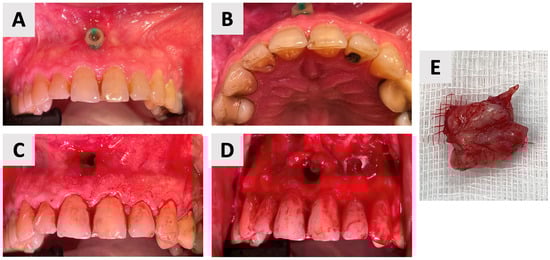

The surgical phase of cyst enucleation (Figure 3) was initiated following the six-month marsupialization period. Local anesthesia was administered using Cook-Waite® Lidocaine HCl 2% and Epinephrine 1:100,000 Injection (Septodont, Saint-Maur-des-Fossés, France). The surgical approach began with intrasulcular incisions extending from the right to left maxillary canines. These were complemented by vertical releasing incisions at the transitional line angles of both maxillary canines, facilitating optimal flap design and access (Figure 3C). A full thickness mucoperiosteal flap was elevated, exposing the bony architecture and revealing the entry point of the previously placed rubber drain (Figure 3D).

Figure 3.

Clinical stages of cyst management and removal. (A) Intraoral view showing the rubber drain in situ just before the end of marsupialization. (B) Palatal view demonstrating resolution of palatal swelling. (C) Surgical flap design with intrasulcular incisions from right to left maxillary canines and vertical releasing incisions at the transitional line angles. (D) Intraoperative view after full thickness mucoperiosteal flap elevation, revealing the bony entry point of the rubber drain. (E) Clinical view of the completely enucleated cyst specimen.

Complete enucleation of the cystic tissue was performed using specialized sinus augmentation curettes (Kohler Medizintechnik GmbH, Stockach, Germany), ensuring thorough removal of all pathological tissue while preserving surrounding vital structures. Following enucleation, the surgical site was thoroughly irrigated with sterile saline to remove any debris and assess for any remaining cystic tissue. The excised specimen (Figure 3E) was immediately fixed in 10% neutral buffered formalin and sent for histopathological examination to confirm the diagnosis.